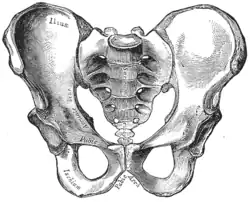

Joints of the pelvis. Anterior view.